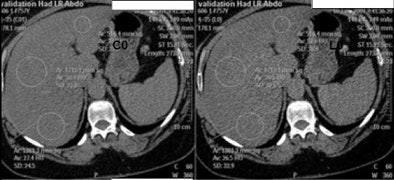

| Ten fatty livers scanned with dual-energy CT demonstrated significant differences between high-energy (HU L1) and low-energy (HU L0) scans; however, two of the four adrenal gland pathologies showed little difference in dual-energy scanning. |

The study included fatty livers, adrenal adenomas, and 19 other microscopic fat-containing lesions such as lipomas, renal angiomyolipomas, and adrenal myelolipomas, Sosna said. According to the results:

- In four adrenal adenomas, HU was lower in low-energy images.

- For all other fatty findings (n = 19), HU was lower in low-energy images (-90 HU) compared to high-energy images (-78).

- The differences were statistically significant (p < 0.05) for each pathology type.

Although the high/low attenuation model worked well for some lesion types such as fatty liver, the differences were difficult to discern in others, such as adrenal adenomas, where only two cases followed the model. Some examples showed no discernable difference in attenuation.